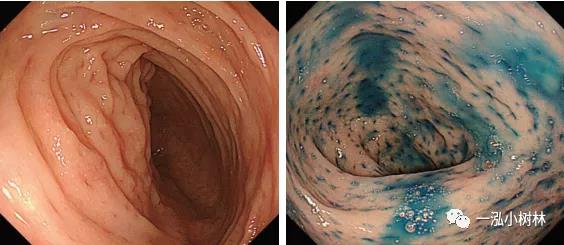

嗜酸性粒细胞性胃肠炎的病因不明,但易引起Th2介导的一系列等过敏反应,引起消化道中IL-5,-13,-15,eotaxin等细胞因子增多,嗜酸性粒细胞和肥大细胞被...